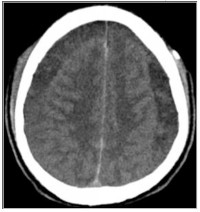

Intracranial subdural haematomas: a rare but disabling complication of spinal anaesthesia

Linda Iroegbu-Emeruem, Idawarifagha Hart, Fiekabo Hart, Uchenna Ajoku, Boma Oyan (Author)

165 - 172